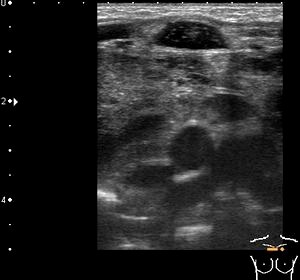

Тимомегалия: что это такое и как проявляется

Раздел: Фотоальбом решений